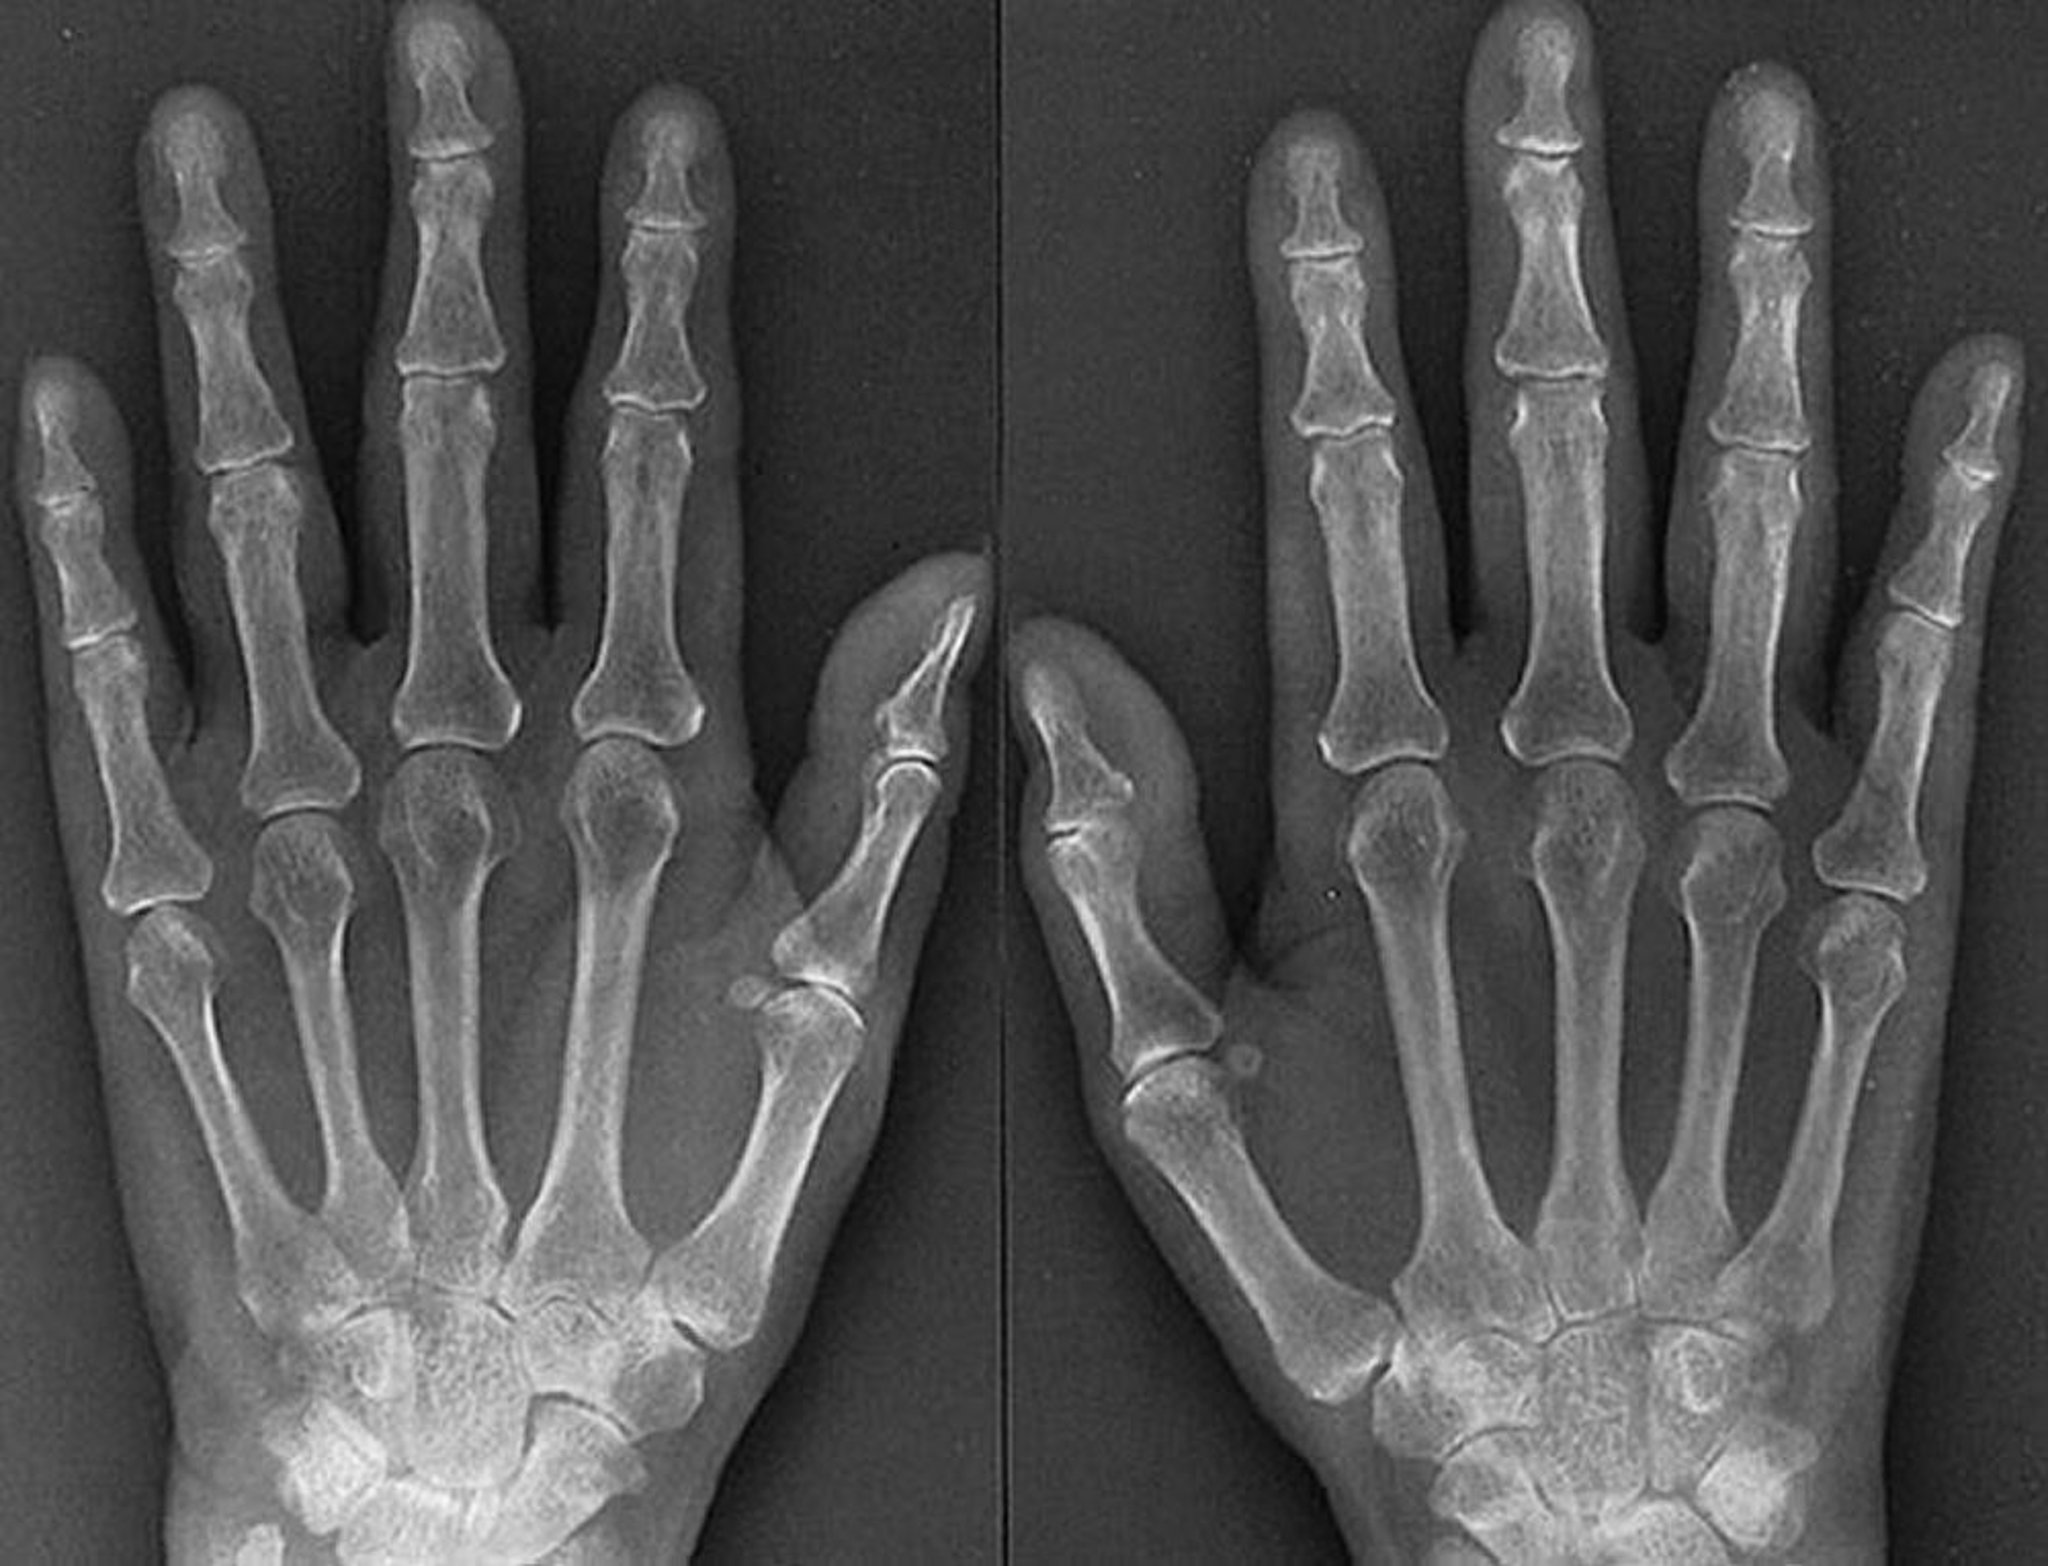

Caratteristiche radiografiche dell'artrite reumatoide precoce

Le caratteristiche di un'artrite reumatoide aggressiva all'esordio, come si vede in questa radiografia di una donna di 61 anni affetta da artrite reumatoide da 1 anno, comprendono evidente gonfiore dei tessuti molli delle articolazioni metacarpofalangea e interfalangea prossimale, osteoporosi periarticolare, restringimento dello spazio articolare simmetrico di diverse articolazioni metacarpofalangee e interfalangee prossimali di entrambe le mani, e sottili erosioni delle articolazioni metacarpofalangee 3a destra e 4a sinistra e destra.